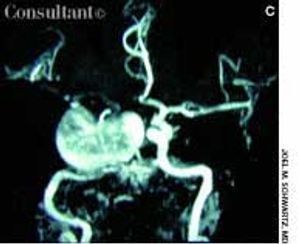

A 69-year-old man with an acute severe headache and nausea was brought to the emergency department. The patient was neurologically intact; an intracerebral hemorrhage was suspected.